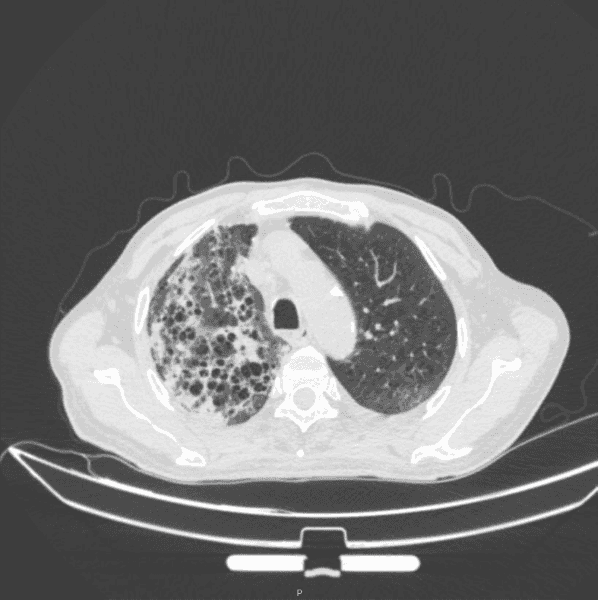

胸部 CT: 两肺间质性炎症,两肺肺气肿(图 3)。

图 3:出院第二十天胸部 CT,两肺间质性炎症,两肺肺气肿患者目前无发热畏寒,无咳嗽咳痰,偶有胸闷气喘,无头晕头痛,无心慌气促,无恶心呕吐,神志清,精神可,饮食睡眠可,大小便正常,体重近期无明显改变案例总结:

所有治疗衣原体的方法相似本例患者主要采用注射用哌拉西林钠他唑巴坦钠和莫西沙星治疗,治疗两周后感染指标明显控制,临床症状明显改善患者因为检测出乙肝小三阳和梅毒特异性抗体阳性,因此前往传染病医院进一步治疗,我们让患者出院后继续口服克拉霉素和莫西沙星,并且在出院的第二十天进行复查,发现患者的实验室各项指标都在明显好转,没有阳性临床症状,CT 也提示较前明显好转,但是患者还没有得到完全恢复,推测可能与患者免疫功能低下有关,我们会对该患者进行后续随访。